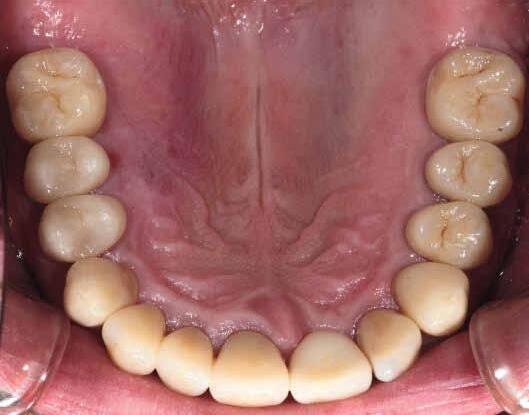

Restoring incisal wear and closing diastema with G-aenial A’CHORD. Courtesy of: Dr Aleksandra Slacan, Poland

Reshaping of teeth and diastema closure with G-aenial A’CHORD. Courtesy of: Dr Andres Silva, Spain